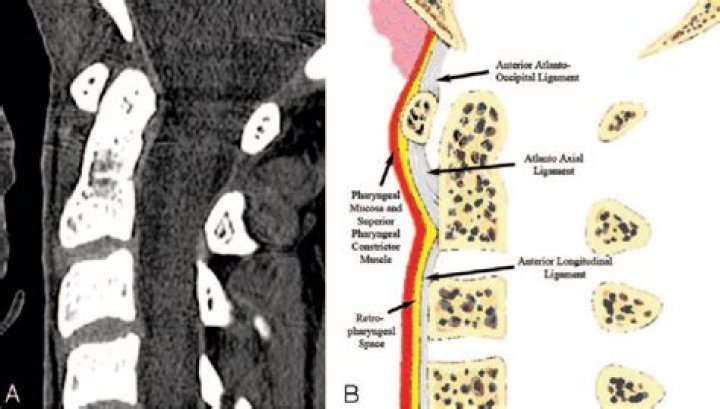

BACKGROUND AND PURPOSE: Analysis of the prevertebral soft tissue (PVST) is helpful in detecting osseous and ligamentous injuries of the cervical spine.